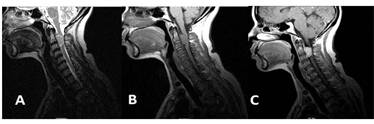

En casi la mitad de la casuística fue leve la captación de la imagen de la lesión. En todos los informes de IRM se estableció el diagnóstico, que predominantemente fue metástasis y meningiomas (fig. 1).

Los meningiomas observados en los pacientes de esta investigación se localizaron fundamentalmente en el segmento lumbosacro, lo que coincidió con lo obtenido por Piñón García et al,7 quienes exhiben entre sus resultados el diagnóstico de un meningioma en la cola de caballo, pero difirió de lo expuesto por otros autores,3,6,9 cuyos hallazgos sitúan este tipo de tumor en los segmentos dorsal y cervical; no obstante, en general existió concordancia en cuanto al resto de las neoplasias extramedulares.

En relación con la intensidad de señales por IRM, se coincidió con la bibliografía sobre el tema6,7 en que los meningiomas habitualmente son isointensos en las secuencias T1 y T2. Otros autores11 refieren que estos se observan iso― o hipointensos en T1 y levemente hiperintensos en T2.

En los dos pacientes con diagnóstico de sospecha de tumor neurógeno, las imágenes fueron isointensas en T1 y T2 o levemente hiperintensas en T2.

Los meningiomas presentan un realce moderado y relativamente homogéneo con una ancha base de adherencia a la duramadre y en la mayoría de los casos se ve el signo de la "cola dural".1,6,13 Las características del tumor varían con el contraste, pues algunos muestran realce marcado, mientras que otros no lo presentan en absoluto.

En esta serie, en casi la mitad de los pacientes se obtuvo una captación leve de la lesión, lo que no fue determinante para registrar un diagnóstico provisional. No obstante, en todos los informes de IRM se reflejó el diagnóstico imagenológico, que fundamentalmente consistió en metástasis y meningiomas. Las metástasis se diagnosticaron en 4 pacientes con tumores primarios conocidos (linfoma, neoplasia de pulmón, seminoma testicular y plasmocitoma extramedular); en otros 5 se sospechó la existencia de metástasis y durante su evolución se confirmó que 4 de estos padecían tumores primarios: linfoma (uno), de próstata (2) y de pulmón (uno).